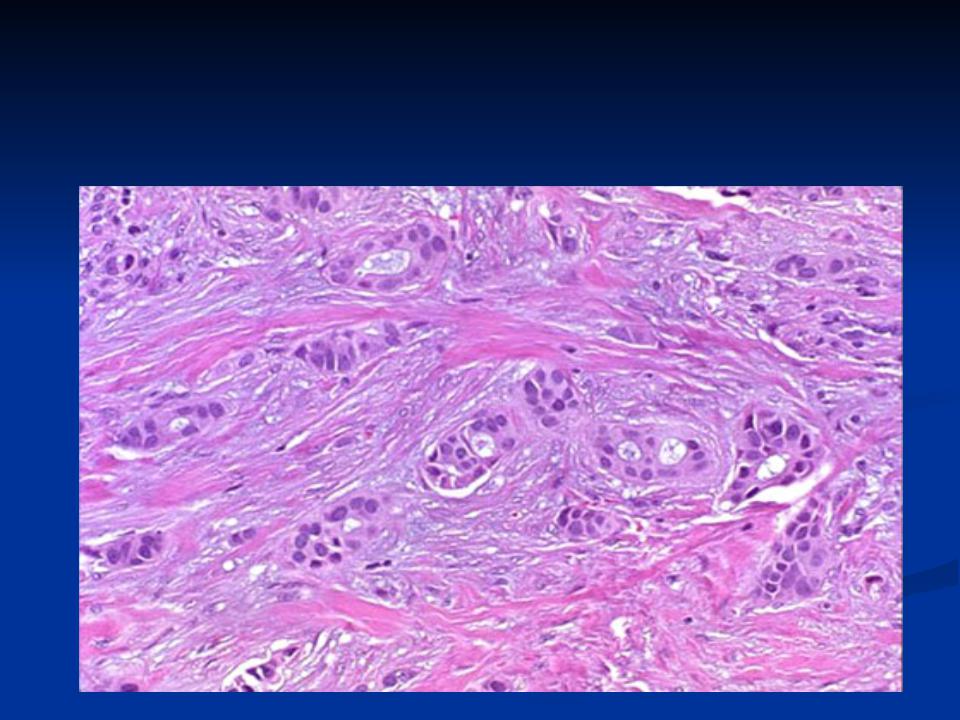

Исследование: микропрепарат молочной железы в медицине

Раздел: Снимки-откровения